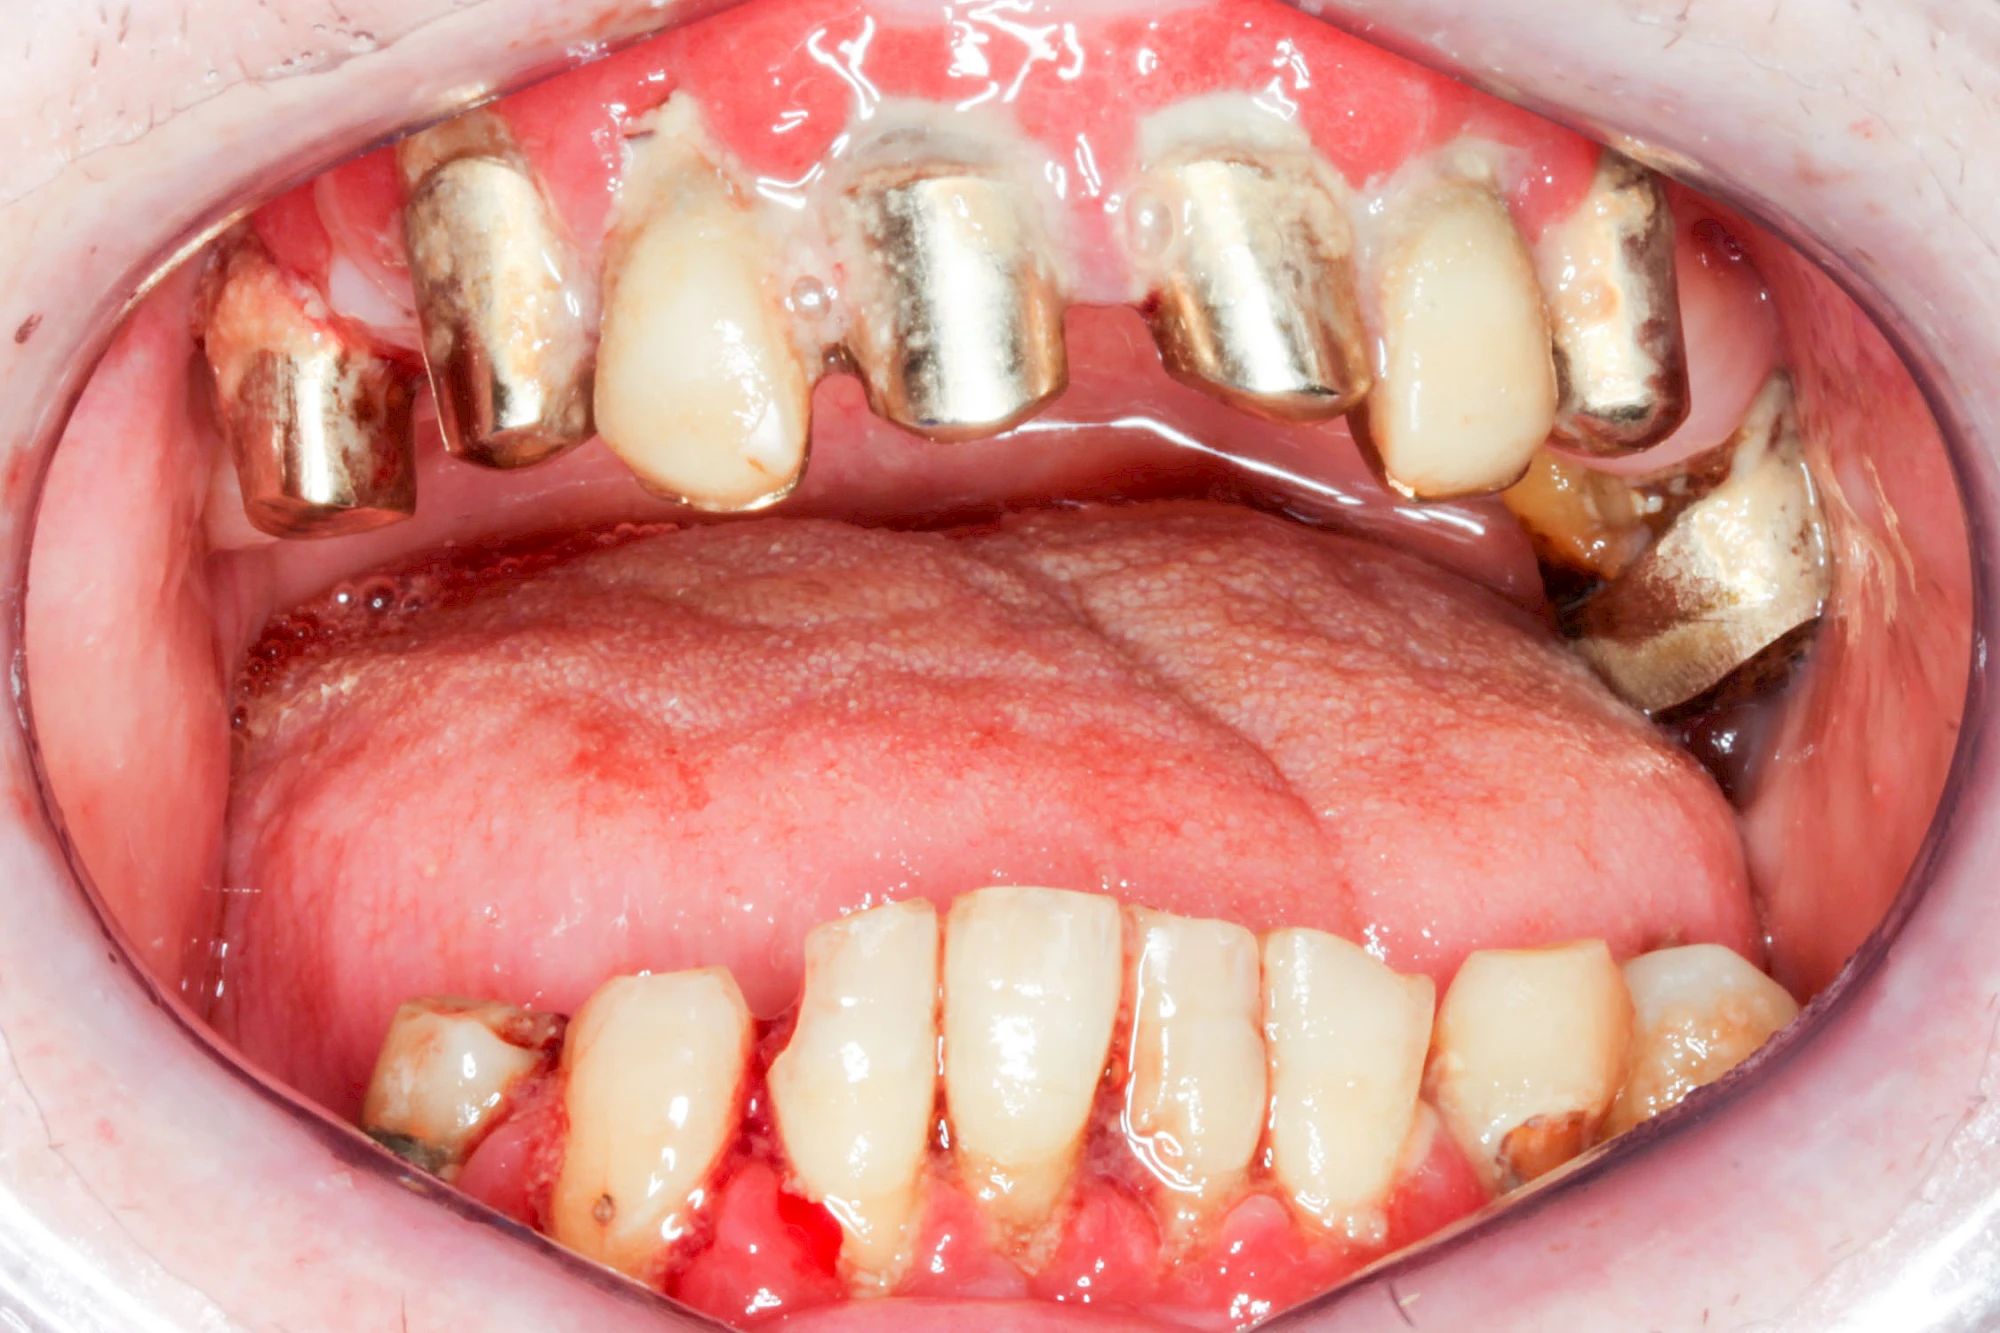

Ist zunächst nur das Zahnfleisch von der Entzündung betroffen, spricht man von Gingivitis. Später, wenn auch der Knochen um die Zähne herum entzündet ist, spricht man von einer Parodontitis. Bei der Parodontitis wird der Knochen nach und nach abgebaut und das Zahnfleisch zieht sich zurück. Die Zahnhälse und Zahnwurzeloberflächen liegen mehr und mehr frei. Die Zähne werden zunehmend lockerer und fallen schließlich aus.

Bakterien in den Zahnbelägen greifen neben den Zähnen auch das Zahnfleisch (Gingiva) und den gesamten Zahnhalteapparat (Parodont) an. Der Körper reagiert mit einer Entzündung, sichtbar als Rötung und Schwellung. Meist blutet das Zahnfleisch z .B. beim Essen oder auch beim Putzen der Zähne.

Ein schlecht eingestellter Diabetes kann das Entzündungsgeschehen noch verstärken. Raucher haben ein 3-5x höheres Risiko für Parodontitis. Das Zahnfleisch ist schlechter durchblutet, weshalb der Körper die Bakterien nicht so gut abwehren kann. So schreitet die Erkrankung schneller voran. Auch E-Zigaretten und Vapes schaden dem Zahnfleisch.